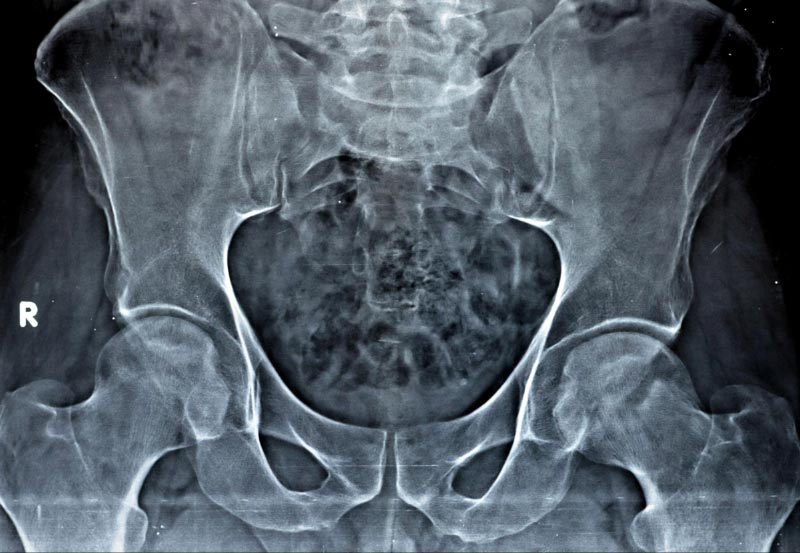

Cấp độ 3 – Trung bình: Khe khớp hẹp nhiều, xuất hiện gai nhỏ cùng hiện tượng cứng xương dưới sụn, kèm theo biến dạng nhẹ ở đầu xương đùi và ổ cối.

Hình chụp X-quang xương chậu cho thấy biến dạng nhẹ tại đầu xương đùi ở bên hông phải.Hình ảnh X-quang khớp biến dạng ở một bên hông.